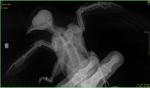

lilamor Опубликовано 3 августа, 2017 Автор #10 Опубликовано 3 августа, 2017 да, если локтевой сустав разрушен, а это по всей видимости так, то это пмж без вариантов. не знаю зачем при закрытом переломе антибиотики, радует конечно, что с покрытием и зачем мелоксикам. ну, видимо, как противовоспалительное. но непонятно в таком случае как покой обеспечивать. а так все верно. к сожалению. Спасибо! С Фиркой всё ясно, будет жить у нас. Сегодня утром привезли еще одного стрижа. Сказал ушиб глаза, но при его осмотре я увидела, что крылья он держит не симметрично. Сделала рентген. Похоже на перелом плечевого сустава? Что посоветуете?И с глазом непонятно. Он иногда приоткрывает его, глаз вроде целый. Перья выпали. Мокрый он потому что в каплях испачкался и я протерла ему голову мирамистином. Капала ципровет.

Anysya Опубликовано 3 августа, 2017 #11 Опубликовано 3 августа, 2017 я не вижу рентген - все очень мелко. но его можно было и не делать. положение плеча не оставляет сомнения - сустав разрушен. пмж.глаз закрывается, потому что черепно-мозговая.так что если птица не идет на усыпление, то стандартное содержание для травмы и чмт. 2х недельный темный бокс, покой, с третьего дня препараты от чмт. просьба, не очень приятная. если птица умрет (чмт непредсказуема) или будет усыплена - у нее идеальные махи. обратите внимание на тему подперивание. Питер остро нуждается в крыльях. на них осенью улетят стрижи и стрижата, сломавшие перья. если что случится - напишите. скажу, как сохранить перо. и отправляйте в Питер.